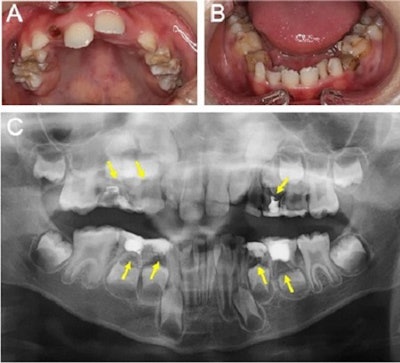

To gain further insight into the source of infection, the boy was referred on September 29 to the hospital's pediatric dentistry department. Intraoral images showed several unfavorable fillings in his baby teeth, and panoramic x-rays showed periapical transmission and root resorption in his upper and lower deciduous molars, the authors wrote.

Clinicians believed that the blood-based brain abscess relied on the infection of the primary lesion. Since the exam revealed no potential causative factor other than dental infection, apical periodontitis of baby teeth was considered the source of multiple brain abscesses.